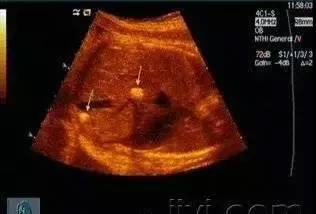

經(jīng)常有病人持超聲或者CT報告到門診咨詢,肝內(nèi)鈣化灶到底是怎么一回事。有些人認為得了肝內(nèi)膽管結(jié)石,更有甚者認為是癌癥,終日惶恐不安。

其實,肝內(nèi)鈣化灶是肝實質(zhì)細胞炎癥后形成的""一般無大礙,一般不需治療。

肝內(nèi)有鈣化點可能是肝內(nèi)膽管壁部分鈣化。它的原因多由于炎癥、結(jié)核等引起,也可能是肝內(nèi)鈣化灶及肝組織局部壞死后的纖維化瘢痕。

肝內(nèi)鈣化灶它與肝內(nèi)膽管結(jié)石一個最重要